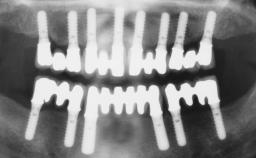

A healthy 31-year-old female patient presented with a failing maxillary left lateral incisor crown. The crown regularly loosened, and the remaining tooth was neither restorable nor rational to treat. The patient had a high smile line, a medium soft tissue biotype with a compromised mesial papilla (shorter than the contralateral one), and a horizontal scar in the buccal soft tissue as a result of past periapical surgery.

| Timing of placement | Immediate Placement (extraction sockets) (Type I) |

| Available apical bone to achieve primary stability | Sufficient height ( ≥ 4 mm) and width (> 2 mm around apex of planned implant) |

| Socket walls | Intact |

| Thickness of buccal wall | less than 2 mm |

| Anticipated residual defect after implant placement | 2 mm or less |

| Loading Protocol | Immediate |

| Implant-supported provisional restoration | Required, elevated esthetic and/or functional demands |